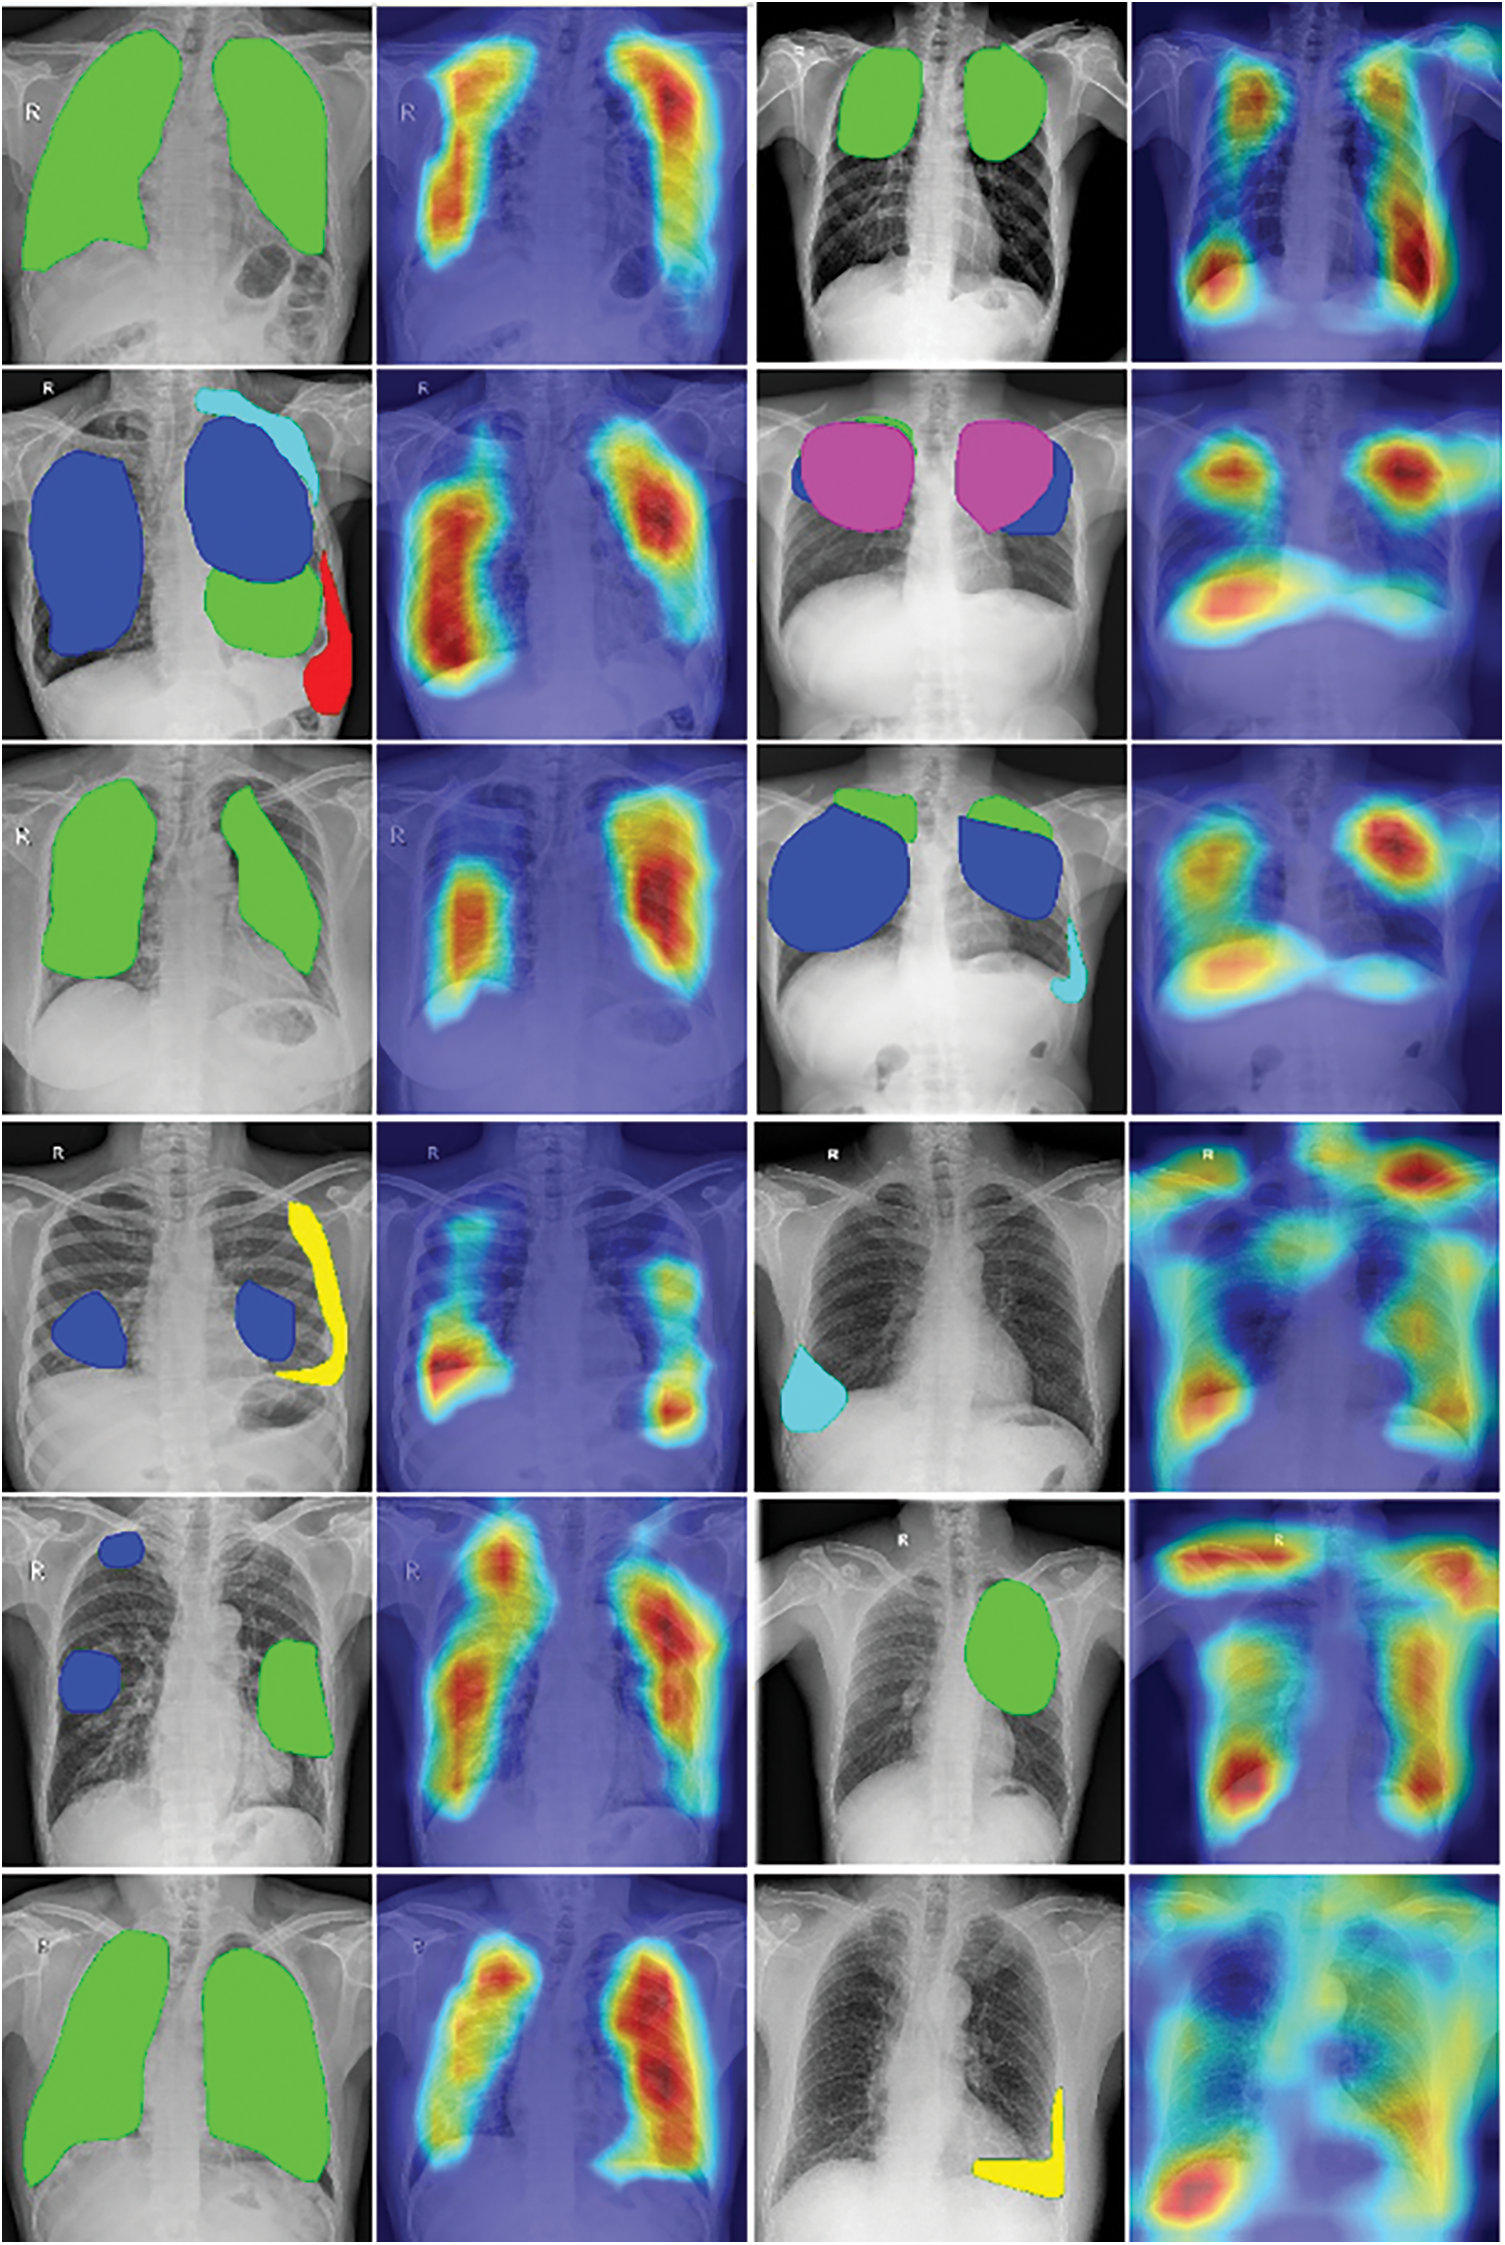

Another evaluation is the heat-map. We applied GradCAM on the trained model to generate heat-maps which would be material to discuss the locations of interest in the whole chest X-ray images. We display them beside the rendering results of annotations.

Fig. 8 describes the visualization of annotation data and heat-map. In each row, from left to right, a sample was present as a pair of annotation rendering and heat-map. In each annotation picture, the green region is Infiltration, the blue region is large nodules, the yellow region is Calcified pleural thickening, the red region is Pleural effusion, the cyan region is Non-calcified pleural thickening, and the pink region is Fibrosis.

Figure 8: The visualization of annotation data and heat-map

From each pair in Fig. 8, we can compare the heat-map vs the display of annotated data. As we can see in the first and second columns in this figure, the heat-maps generated by the Grad-CAM algorithm pointed out lesion regions rather correctly in chest X-ray images. This might be some good visual evidence for the radiologist’s viewpoint. But in the third and fourth columns, the focused regions are more complex. Some heat-maps present not only the locations of annotated data but also the other regions in the lung of patients, the other heat-maps give diffused information around the chest X-ray images.

Based on the professional opinion of radiologists, tuberculosis has various visual influences on the chest X-ray image, which come from different causes. The diagnosis result might also depend on the relationship between locations of influences, for example, symmetry, inside. Moreover, different regions also can overlap and the distribution of lesions is unbalanced. Another is the difference if we compare with visual information in normal images, such as the cars, and dogs in photos. In short, the complex visualization of heat-maps could come from many reasons. So in our opinion, the heat-maps, which presented the focused locations of trained models, have achieved some initial success in indicating the visual tuberculosis features in chest X-rays but there were not enough and it has still needed more studies to be able to explain suitably with the radiologist knowledge.